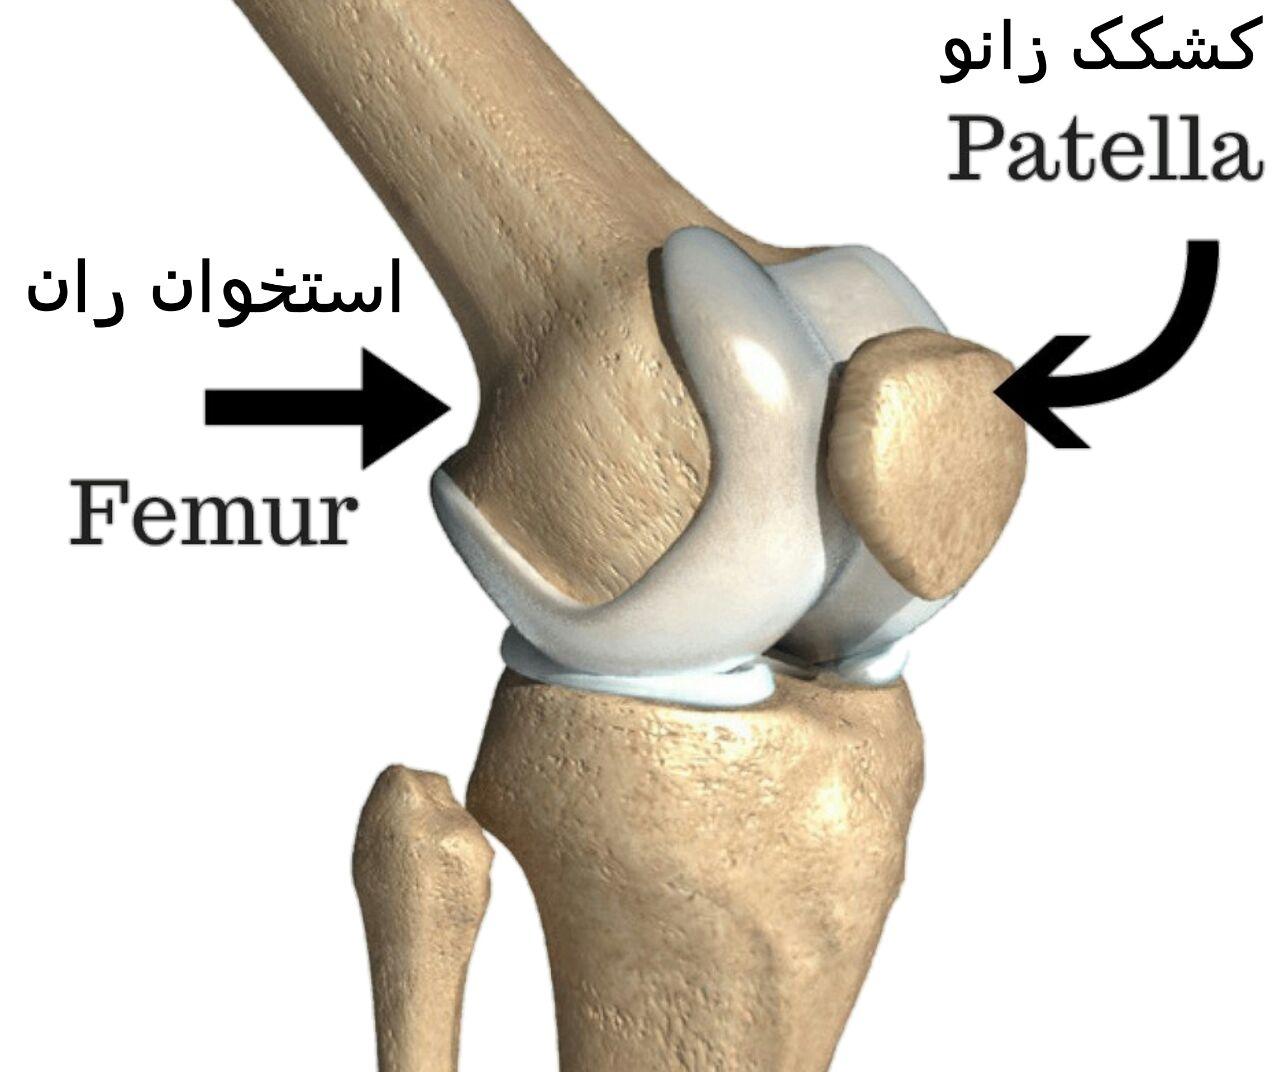

قیمت: 52٬500 تومان - دسته بندی فایل: پاورپوینتدانلود پاورپوینت آسیب acl یا رباط صلیبی قدامی در زانو

خرید پاورپوینت حرفه ای با موضوع آسیب acl یا رباط صلیبی قدامی در زانو از لوکس فایل

قیمت: 52٬500 تومان - دسته بندی فایل: پاورپوینتدانلود پاورپوینت آشنایی با کندرومالاسی پاتلا

خرید پاورپوینت حرفه ای با موضوع آشنایی با کندرومالاسی پاتلا از لوکس فایل